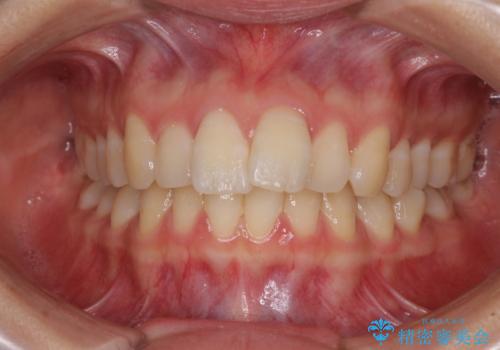

- 前歯の突出感を気にして来院された患者様です。

左右ともに奥歯の咬み合わせが上顎前突となっており、上顎前歯が飛び出している状態でした。

奥歯の咬み合わせ改善が必要であるため、マウスピース矯正より確実に達成のできるワイヤー矯正にて治療を行うこととしました。